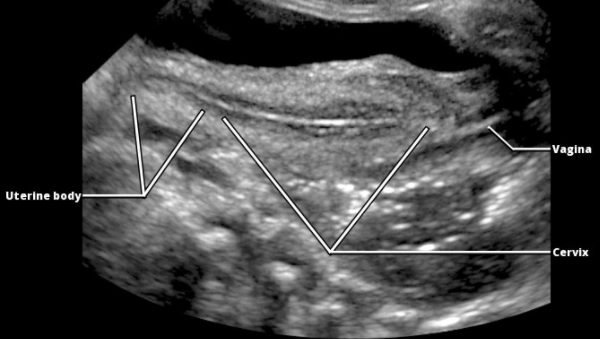

- Le Col plus large que le corps

- Corps < Col (1:2)

- Corps = Col (1:1)

- Corps > Col (2:1)